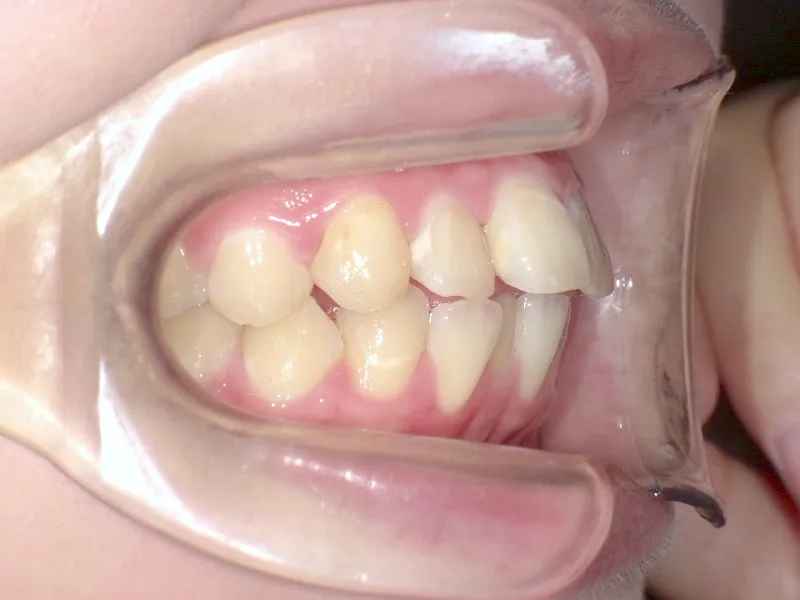

初診時年齢 19~29歳 (女性) 主訴 上下がガタガタ・出っ歯

診断名 叢生・上下顎前突 装置名

上下の歯並びがガタガタで口元が出ています。

何年か経過後、ガタガタと口元が気になると受診されました。

再治療の時は、上の歯は前から見えにくいオリジナル固定装置、下の歯はマルチブラケット装置を使用し、治療しました。

治療回数62回、1年6ヶ月の治療期間で矯正治療を終了しました。

前回の治療で歯の根っこの部分の位置を治していたので、全部前から付けるのではなく最低限見える装置で治せました。